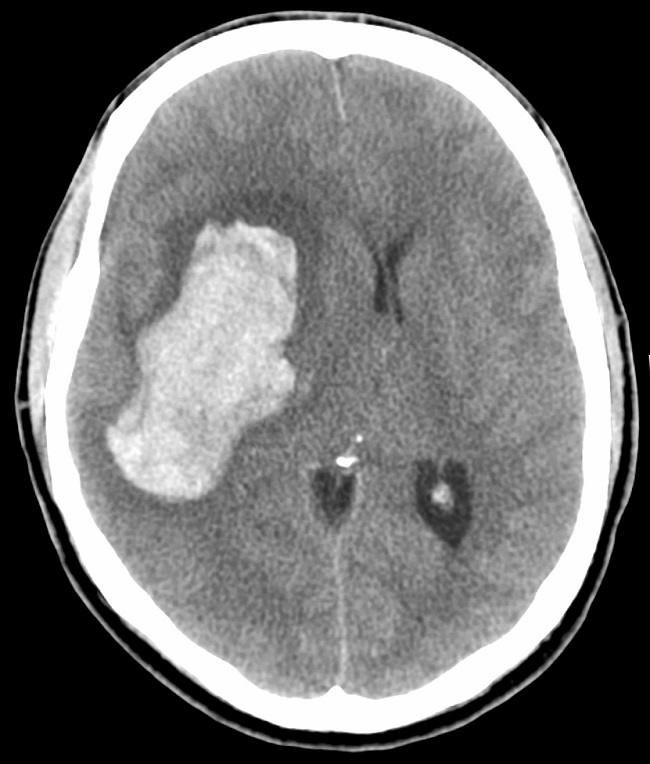

Patofisiologi Perdarahan Intrakranial - Alomedika

www.alomedika.com

alomedika